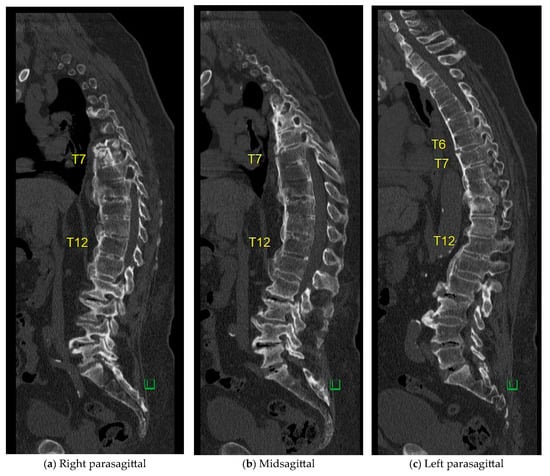

The case of an 81-year-old male, suffering from ischemic heart disease, atrial fibrillation, hypertension, morbid obesity, and gout, illustrates a unique treatment approach. He presented to the E.R. three days after a backward fall, having sustained an extension-type injury to T10–T11 a year and a half prior, which was treated non-operatively due to a very high operative risk. In the current fall, a new extension-type injury was identified at the T6–T7 level. He experienced back pain without radiating symptoms and had a long-standing foot drop but no new nerve deficit. His CT scans are shown in Figure A1. At a 4-month follow-up visit to the outpatient clinic, standing X-rays were performed, further confirming the stable healing of the fracture as shown in Figure A2.

Figure A1. Parasagittal (a,c) and Mid-sagittal (b) CT reconstructions obtained one year following a T9–T10 extension-type injury and five days after a subsequent backward fall. A new extension-type injury at the T6–T7 level is identified. No involvement of the posterior elements is observed.